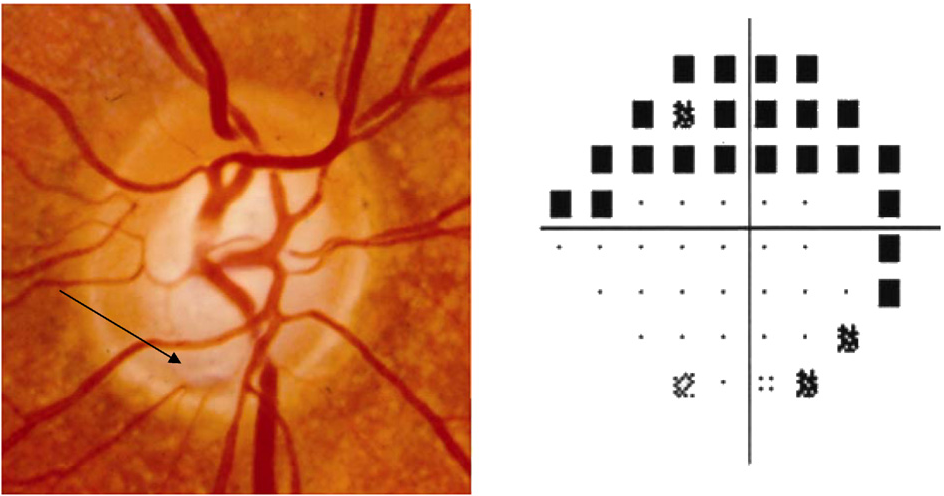

1/3에서는 시신경유두의 상극단의 귀쪽에서,

2/3에서는 시신경유두의 하극단의 귀쪽에서, 발견되는데,

APON을 가진 녹내장환자의 96%에서 시야 중심 5도내의 짙은 시야 결손이 동반되며,

APON을 가진 녹내장환자의 경우 APON이 없는 환자보다 유의하게 손상이 진행되며, 시시녕 유두출혈도 더 많이 동반됩니다.

<Disc notching 과의 차이>

시신경유두 패임(Optic disc notching)의 경우, 전반적으로 더 넓고 얕은 패임을 보이며, 유두연으로 확장하는 모습인데,

후천성시신경유두오목의 경우, 국소적으로 좁고 깊은 패임으로, 유두연에 닿고 있는 패임의 양상입니다.